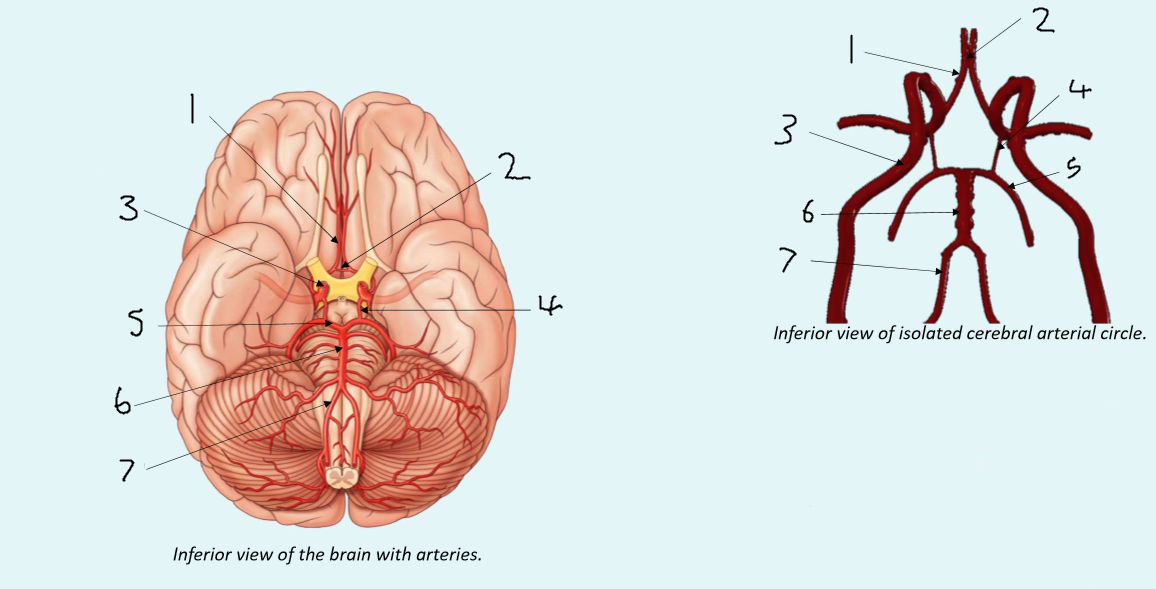

What is 1?

anterior cerebral artery

What is 2?

anterior communicating artery

What is 3?

internal carotid artery

What is 4?

posterior communicating artery

What is 5?

posterior cerebral artery

What is 6?

basilar artery

What is 7?

vertebral artery